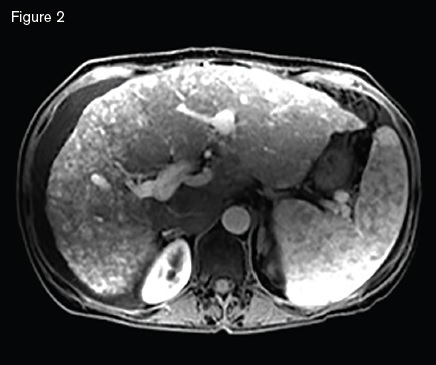

Magnetic resonance image showing a macronodular liver with diffuse arteriovenous malformations s involving both hepatic lobes, ascites, and splenomegaly.

Magnetic resonance image showing a macronodular liver with diffuse arteriovenous malformations s involving both hepatic lobes, ascites, and splenomegaly.

A 51-year-old woman with HHT was referred for management of recurrent epistaxis, GI bleeding, iron deficiency anemia, large bilobar hepatic AVMs, and worsening ascites. Gastric AVMs were previously managed with endoscopic argon plasma coagulation. She required regular intravenous iron and occasional blood transfusions to maintain a hemoglobin of seven to 10 g/dL. Elevated liver enzymes two years earlier prompted an ultrasound that demonstrated hepatic AVMs. Magnetic resonance imaging (Figure 2) demonstrated a macronodular liver with diffuse AVMs involving both hepatic lobes, ascites, and splenomegaly. Angiogram demonstrated large hepatic arteries with shunting primarily from hepatic artery to portal vein (Figure 3). She primarily reported weakness, dyspnea on exertion, and worsening ascites requiring weekly six- to seven-L paracentesis.